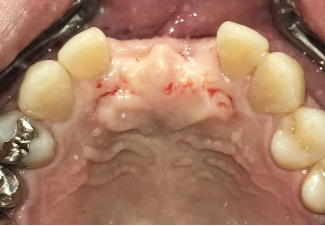

レントゲンで詳しく診てみると、虫歯が歯根のほうまで進行し、保存することができないことがわかり、抜歯しました。抜歯後、骨が大きく欠損していましたので、骨造成を行いインプラントを2本埋入しました。

Before

【抜歯後】

After